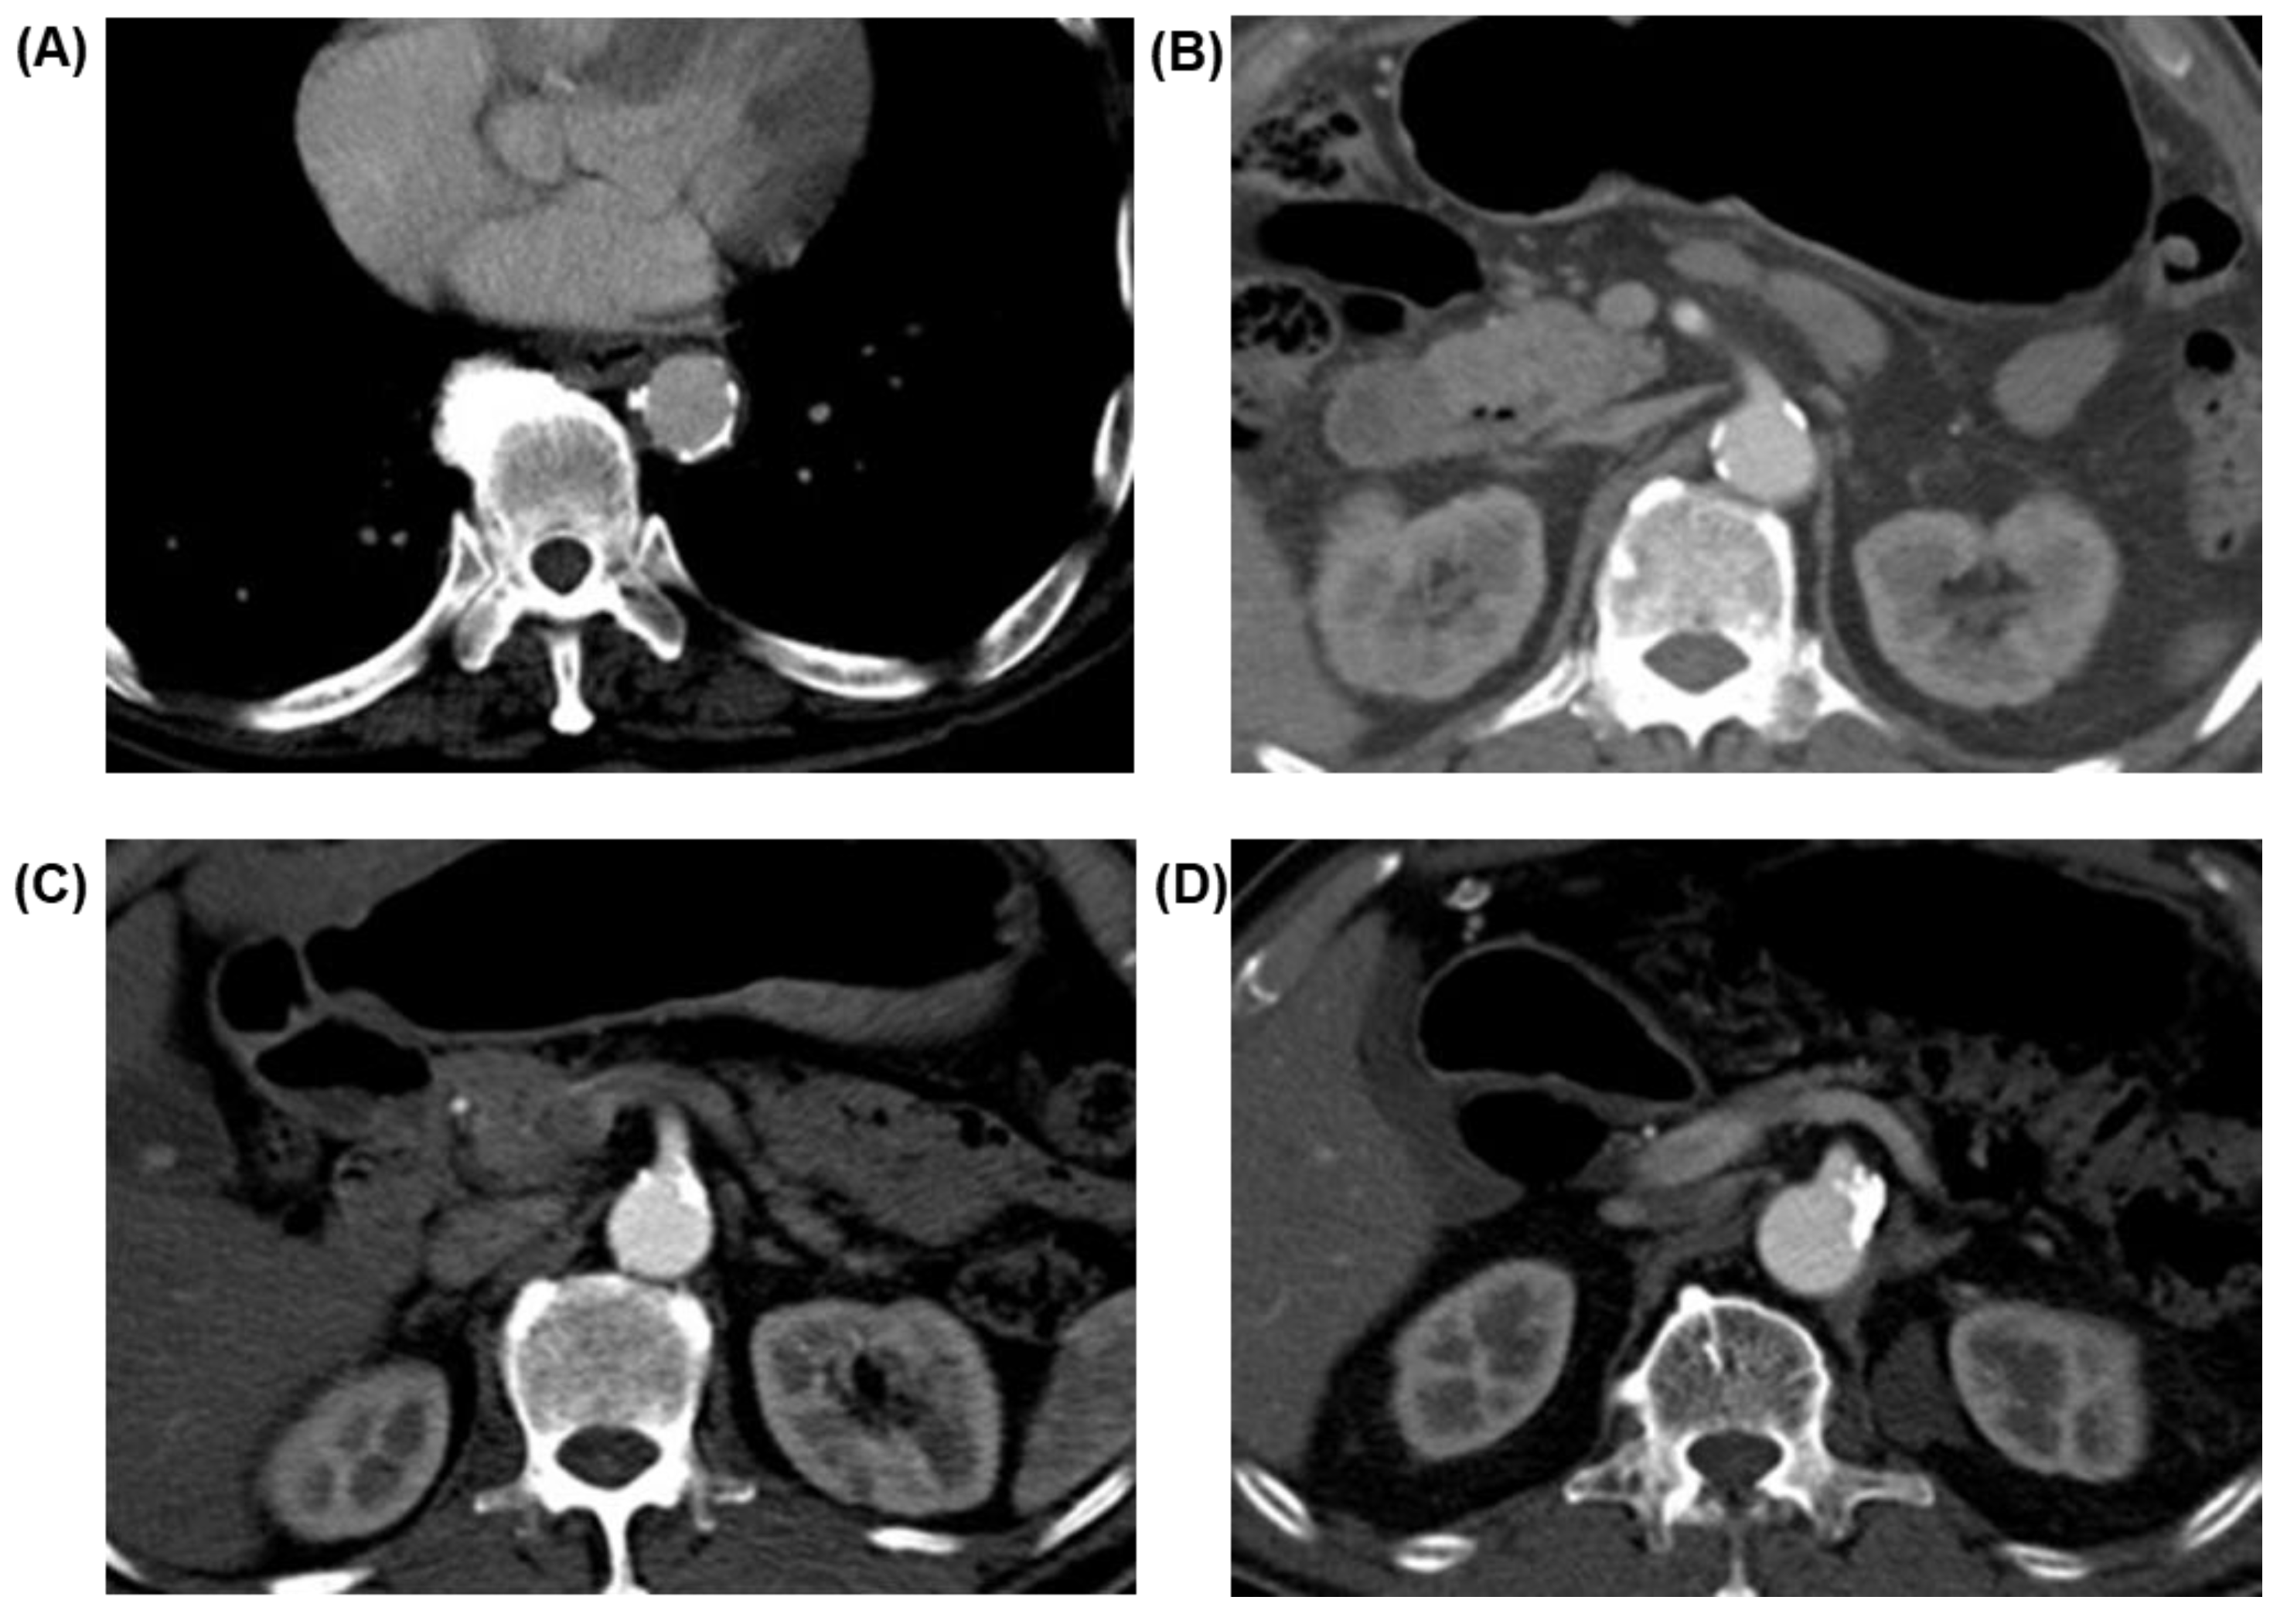

2.4. Image Acquisition and Evaluation